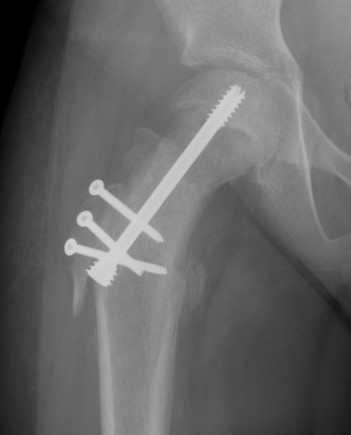

Intertrochanteric / Southwick

Technique

- biplanar

- valgising / flexion / internal rotation

- removal anterolateral bone wedge below LT

Advantage

- no AVN / safest

- improves hip motion

Disadvantage

- worsens LLD

- difficult THR